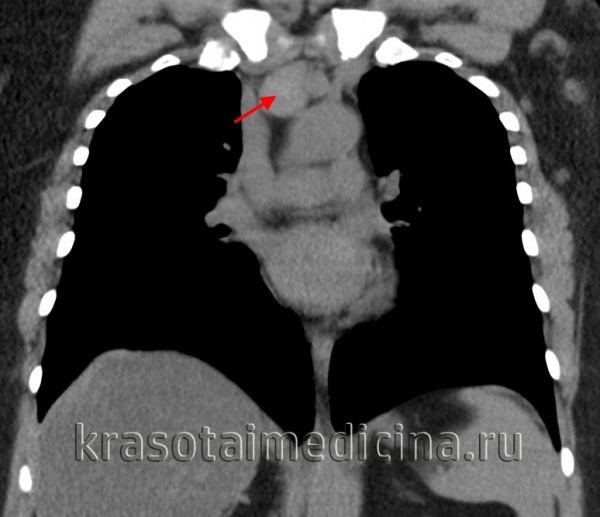

Лимфомы медиастинальной локализации не всегда диагностируются при рентгенологическом обследовании. Компьютерная томография, более детально, чем обзорная рентгенография позволяет рассмотреть конгломерат опухоли, увеличение лимфоузлов средостения, вовлечение паратрахеальных, трахеобронхиальных, прикорневых лимфатических узлов. Диагностическая значимость магнитно-резонансной томографии в верификации лимфом средостения признается не всеми авторами.

КТ ОГК. Объемное образование в средостении (патологически измененный лимфоузел), подтвержденная лимфома.